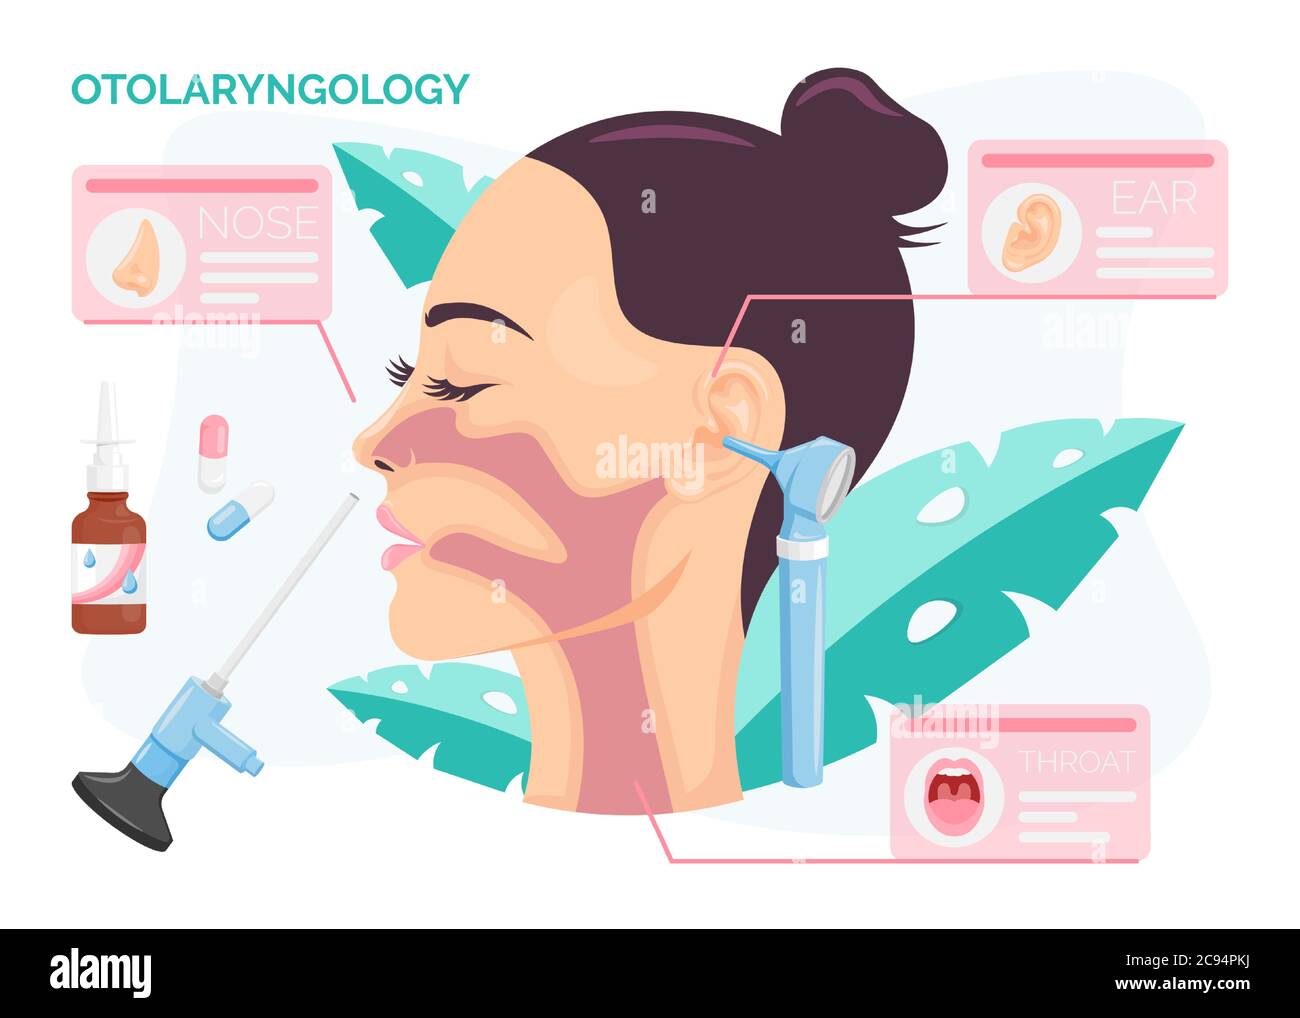

RF2C94PKJ–Otolaryngologie concept. Femme subissant un traitement de l'oreille, du nez ou de la gorge à la clinique ORL, illustration vectorielle isolée dans le style de dessin animé plat